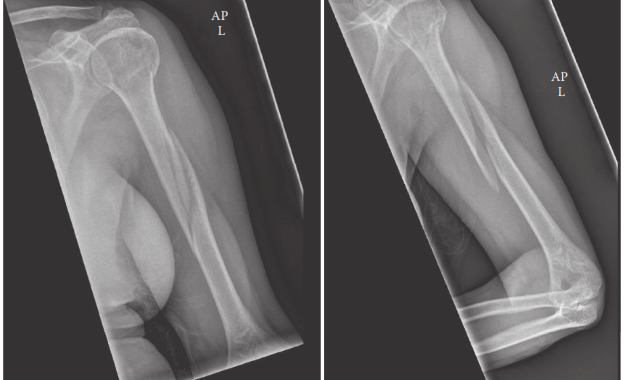

- الأشعة السينية (X-rays): هي الخطوة الأولى والأساسية في التشخيص. يتم التقاط صور للأشعة السينية من عدة زوايا (أمامية خلفية وجانبية) للذراع بأكملها، بما في ذلك مفصلي الكتف والكوع. تساعد هذه الصور في تأكيد وجود الكسر، وتحديد نوعه (عرضي، مائل، حلزوني، مفتت)، وموقعه، ودرجة إزاحته.

- التصوير المقطعي المحوسب (CT Scan): قد يُطلب التصوير المقطعي في حالات الكسور المعقدة أو المفتتة، أو إذا كان هناك اشتباه في امتداد الكسر إلى المفاصل (على الرغم من ندرة ذلك في كسور منتصف العضد). يوفر التصوير المقطعي صورًا ثلاثية الأبعاد أكثر تفصيلاً للعظم، مما يساعد في التخطيط الجراحي الدقيق.

يُعد التخطيط المسبق للعملية الجراحية أمرًا بالغ الأهمية. يقوم الأستاذ الدكتور محمد هطيف بتقييم صور الأشعة السينية والتصوير المقطعي بدقة، ويختار نوع الغرسة (الشريحة أو المسمار) وحجمها المناسبين، ويناقش المخاطر المحتملة (مثل إصابة العصب الكعبري، عدم الالتئام، العدوى، الحاجة إلى جراحة مراجعة) مع المريض.